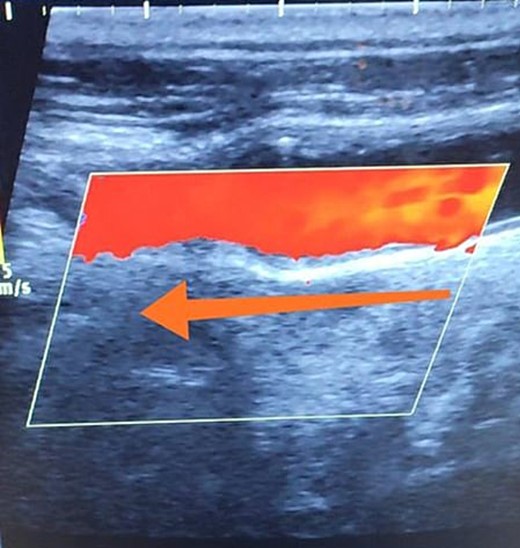

A 65-year-old male presented with recurrent transient ischemic attacks (TIAs), characterized by severe balance disturbances, transient alterations in consciousness, and visual obscurations. Clinical examination revealed high blood pressure in the right arm and absent left radial and brachial artery pulses. Vital signs were normal. Laboratory tests are analyzed as follows: urea: 22 mg/dl, glucose: 150 mg/dl, cholesterol: 199 mg/dl, and triglycerides: 222 mg/dl. A medical history of type 2 diabetes mellitus (DT2), hypertension (HTN), hyperlipidemia, ischemic heart disease, and a heavy smoking history were recorded. Five years before presentation, the patient underwent coronary stenting. Medication history included metformin 1000 mg, aspirin 81 mg, rosuvastatin 40 mg, and ramipril 5 mg. Neck duplex ultrasound (DU) showed normal flow direction and insignificant atherosclerotic plaques in the left internal carotid artery (CA) and left external CA (Figs 1 and 2), normal common CA (Fig. 3), a completely inverted flow direction in the left VA (Fig. 4) that suspected a significant ostial lesion in the left SCA. Multi-slice computed tomography angiography demonstrated 99% stenosis at the left SCA origin and confirmed the presence of SSS (Fig. 5). A balloon angioplasty was unsuccessfully attempted to expand the left SCA. A left carotid VA bypass surgery was performed, and a vascular graft was used to establish a blood flow pathway between the left VA and the left CA. By follow-up, the patient was stable without complications.

Duplex ultrasound showing a normal flow direction in the common carotid artery.

With a prevalence ranging from 0.6% to 6.4%, SSS is considered a rare phenomenon, and high suspicion is required for diagnosis [2, 5]. The basilar artery is formed by the two vertebral arteries and connects to the brain’s anterior circulation, comprising the Willis circle. However, a steno-occlusive lesion of the proximal SCA may lead to limited blood flow to the upper extremity. Consequently, blood flows through the contralateral VA to the basilar artery, around the circle of Willis, and then descends through the IVA to supply the affected upper extremity, leading to upper limb and vertebrobasilar insufficiency. This altered physiology manifests in signs and symptoms constellation defining SSS [1, 4]. A total of 82.3% of lesions primarily affect the left side as a result of the sharper curvature at the origin of the left SCA, which increases blood flow turbulence and promotes atherosclerotic plaque formation [1, 2, 5–7]. In this case, a patient with retrograde left VA flow on DU is presented (Fig. 4). Most patients are asymptomatic due to developing collateral circulation [2]. However, it may manifest with arterial insufficiency affecting the upper limb (paresthesia, weakness, and claudication), the brain (vertigo, dizziness, diplopia, ataxia, dysarthria, slurred speech, and syncopal episodes) [1, 2, 5, 7], or the heart if the patient has a coronary artery bypass graft supplied by the internal mammary artery [6]. Our patient suffered from recurrent TIA, manifested as severe balance disturbances, transient altered mental status, and amaurosis fugax (transient vision loss). The most common diagnostic tests for SSS are the DU and TDU due to their accessibility and low cost, which show the subsequent retrograde blood flow in the IVA. Additionally, MRA or CT angiography is used as a confirmatory modality [1, 2, 5–8], but the gold-standard is conventional cerebral angiography [1]. A difference in blood pressure readings between arms >20 mmHg is a significant and noticeable sign. In our case, neck DU showed an inverted left VA flow direction (opposite to the carotid) (Fig. 1). MSCT confirmed the diagnosis of SSS, demonstrating a significant ostial lesion in the left SCA. Conservative management is preferred with minimally symptomatic patients by reducing risk factors like a specific regime and treating comorbidities such as: HTN, DT2, hyperlipidemia, and smoking cessation as a part of minimizing morbidity and preventing complications [1, 2, 5–8]. Surgery is recommended for severe and untreated cases through percutaneous intervention or surgical revascularization by using vascular bypass accompanied by angioplasty and stenting [1, 2, 5–7]. In our case, expanding the left subclavian by catheterization did not succeed; however, a left carotid-vertebral bypass was successfully performed. The most common complications are stroke (ranging from 0.4% to 4.7%) due to distal emboli, thrombosis or bleeding and rupture because of aggressive catheter or wire manipulation [1, 7]. In our case, the patient continues on HTN and DT2 medications: ramipril 5 mg, rosuvastatin 40 mg, aspirin 81 mg, and metformin 1000 mg.